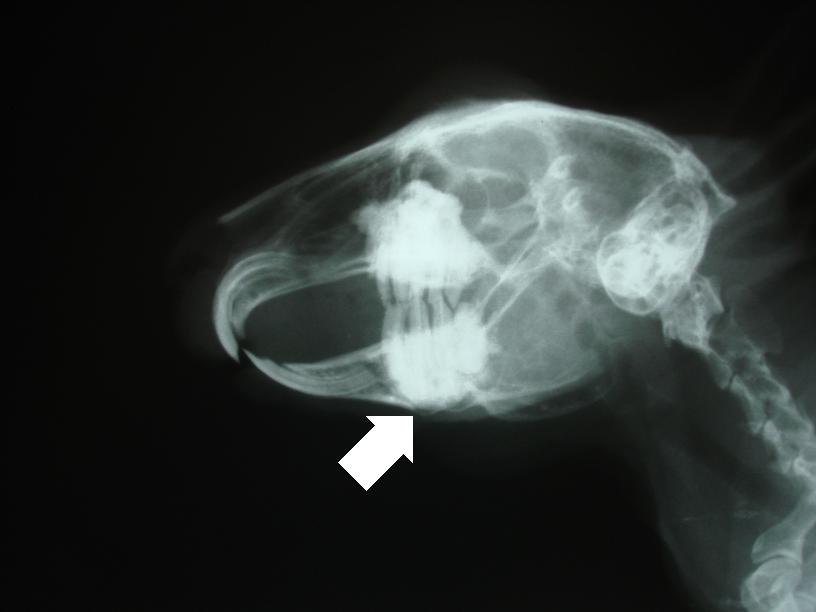

RTG snímek zobrazuje přerůstání zubních kořenů a rozrušování kosti spodní čelisti.

RTG snímek čelisti